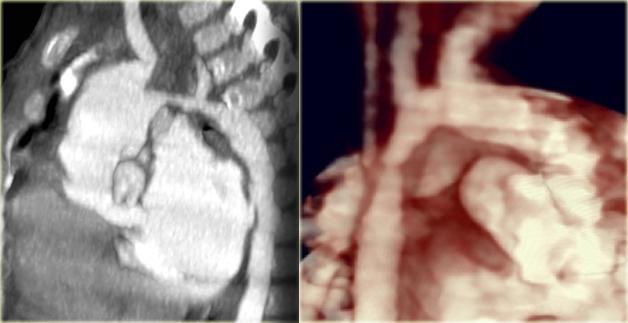

On the left a 2 month old boy with heart failure.

First study the image, then continue

- Striking discrepancy between diameter of ascending and descending aorta.

The diagnosis is coarctation, which is nicely demonstrated on the posterior view of the reconstruction.

First study the axial image followed by the sagittal reconstruction, then continue.

The findings are:

- Big internal mammarian arteries on the axial image due to a high grade stenosis as a result of a coarctation. Probably could not make the diagnosis based on the axial images alone.

- Post-ductal coartation only seen on sagittal reconstruction.

- Intercostal collaterals.

The intercostal collaterals typically occur between the 3rd and the 8th rib.